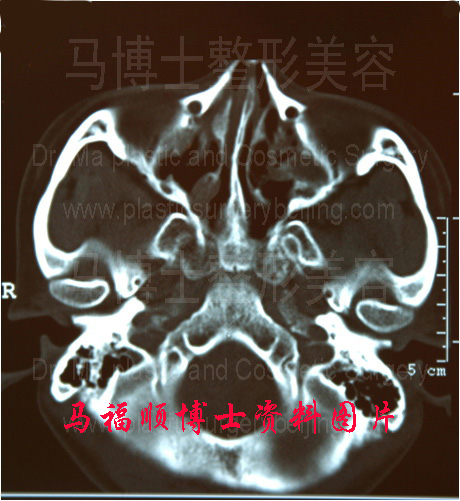

颧骨颧弓舒平术是将颧骨颧弓进行多段截骨,只有这样才可以将颧弓的弓度进行自然的降低。数学原理告诉我们当颧弓的截骨处无穷多的时候,就可以非常平滑地使颧弓弓度变化、愈合后完全看不出截骨的痕迹。但临床工作中不可能做到将颧弓进行无穷多处的截骨,从而使截颧弓弧度完全自然。我们只能做到多处截骨,尽量使愈合后的颧弓看不出截后变形的痕迹。临床应用中发现由于人体的骨骼本身就是不平滑的,颧弓的弓度也不是数学上的完美弧形,所以舒平后的颧骨颧弓再进行CT检查时时也完全看不出截骨的痕迹。

整形前颧弓向两侧突出明显,致面部宽度大。颧骨颧弓舒平整形术后,颧弓的弧度变直,再不向两侧突出,面部宽度变小。虽然颧弓弓度变化明显,但CT片上看不能颧骨颧弓有任何动过手术的痕迹。